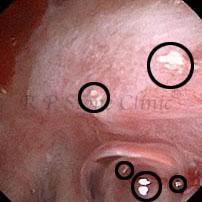

Kidney stone is a solid mass of CRYSTALS. It is the process of crystallization which initiates the formation of kidney stones. This happens in nephrons or units of kidney. Once a small crystal is formed, it can both grow & unite with other crystals leading to the formation of small concretion which eventually forms a stone. Once these large crystals detach from the collecting ducts, the process of stone formation starts in the renal collecting system. A recurrent kidney stone former is advised to know a little bit about something known as Randall’s plaque. Alexander Randall discovered plaques on the renal papillae eight decades back based on examination of 1154 pairs of autopsied Kidneys. He described these renal papillary lesions as cream colored or milk patch areas composed of calcium phosphate & calcium carbonate. These plaques could act as NIDUS for formation of KIDNEY STONE. Calcium Oxalate stone can form on this nidus & then detaches from this plaque to become a free floating stone in the collecting system of kidney

These images are taken as snap shots from the video recording of RIRS Surgery done at our hospital. These are Randall’s Plaques seen with Digital FLEX XC & Digital FLEX XC S. The cream or whitish patches are seen on the tips of RENAL PAPILLAE as seen in images below.

Randall’s Plaques may lead to the formation of Stones.

Those kidney stone patients who have Randall’s Plaques in their kidneys are more likely to form stones again (Recurrent Stones).

Stone Patients in whom Randall’s Plaques are detected at the time of RIRS Surgery should undergo regular ultrasound examination for early detection of stones.

Patients of Stones with Randall’s Plaques in their Kidneys should drink plenty of fluids in addition to Orange Juice & Lemonade.